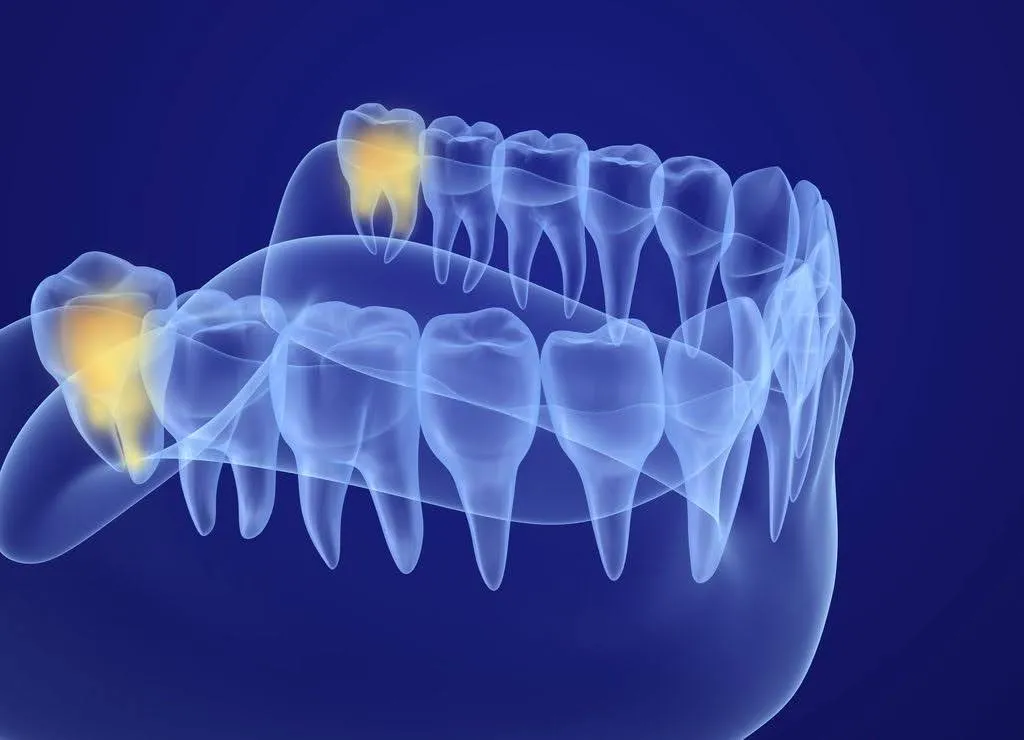

親知らずを抜かない方がいい場合

親知らずが真っ直ぐに生えている口腔内

• 親知らずが真っすぐに生えていて清掃状態もいい場合

• 上下の歯がしっかりとかみ合っている場合

以上のように正常に生えている親知らずは、これからも使用できます。